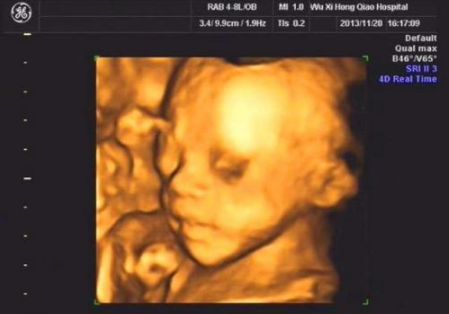

四维彩超男宝宝图片

四维彩超男宝宝图片,四维单子上女孩标志